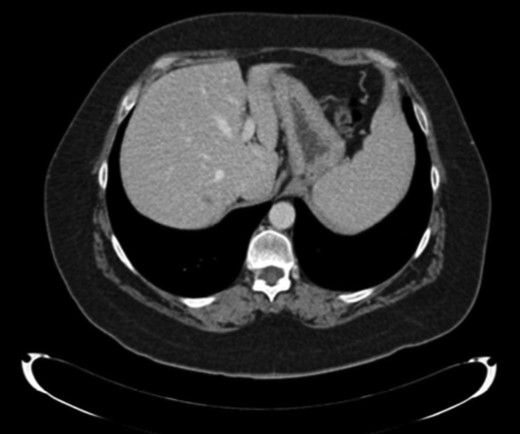

A new hepatic node in segment VII was observed nine months later (Fig. 3). Systemic treatment was administrated with cisplatin (75 mg/m2) and cetuximab for three months. At the end of the treatment, another non-anatomical metastasectomy with free margins was performed.